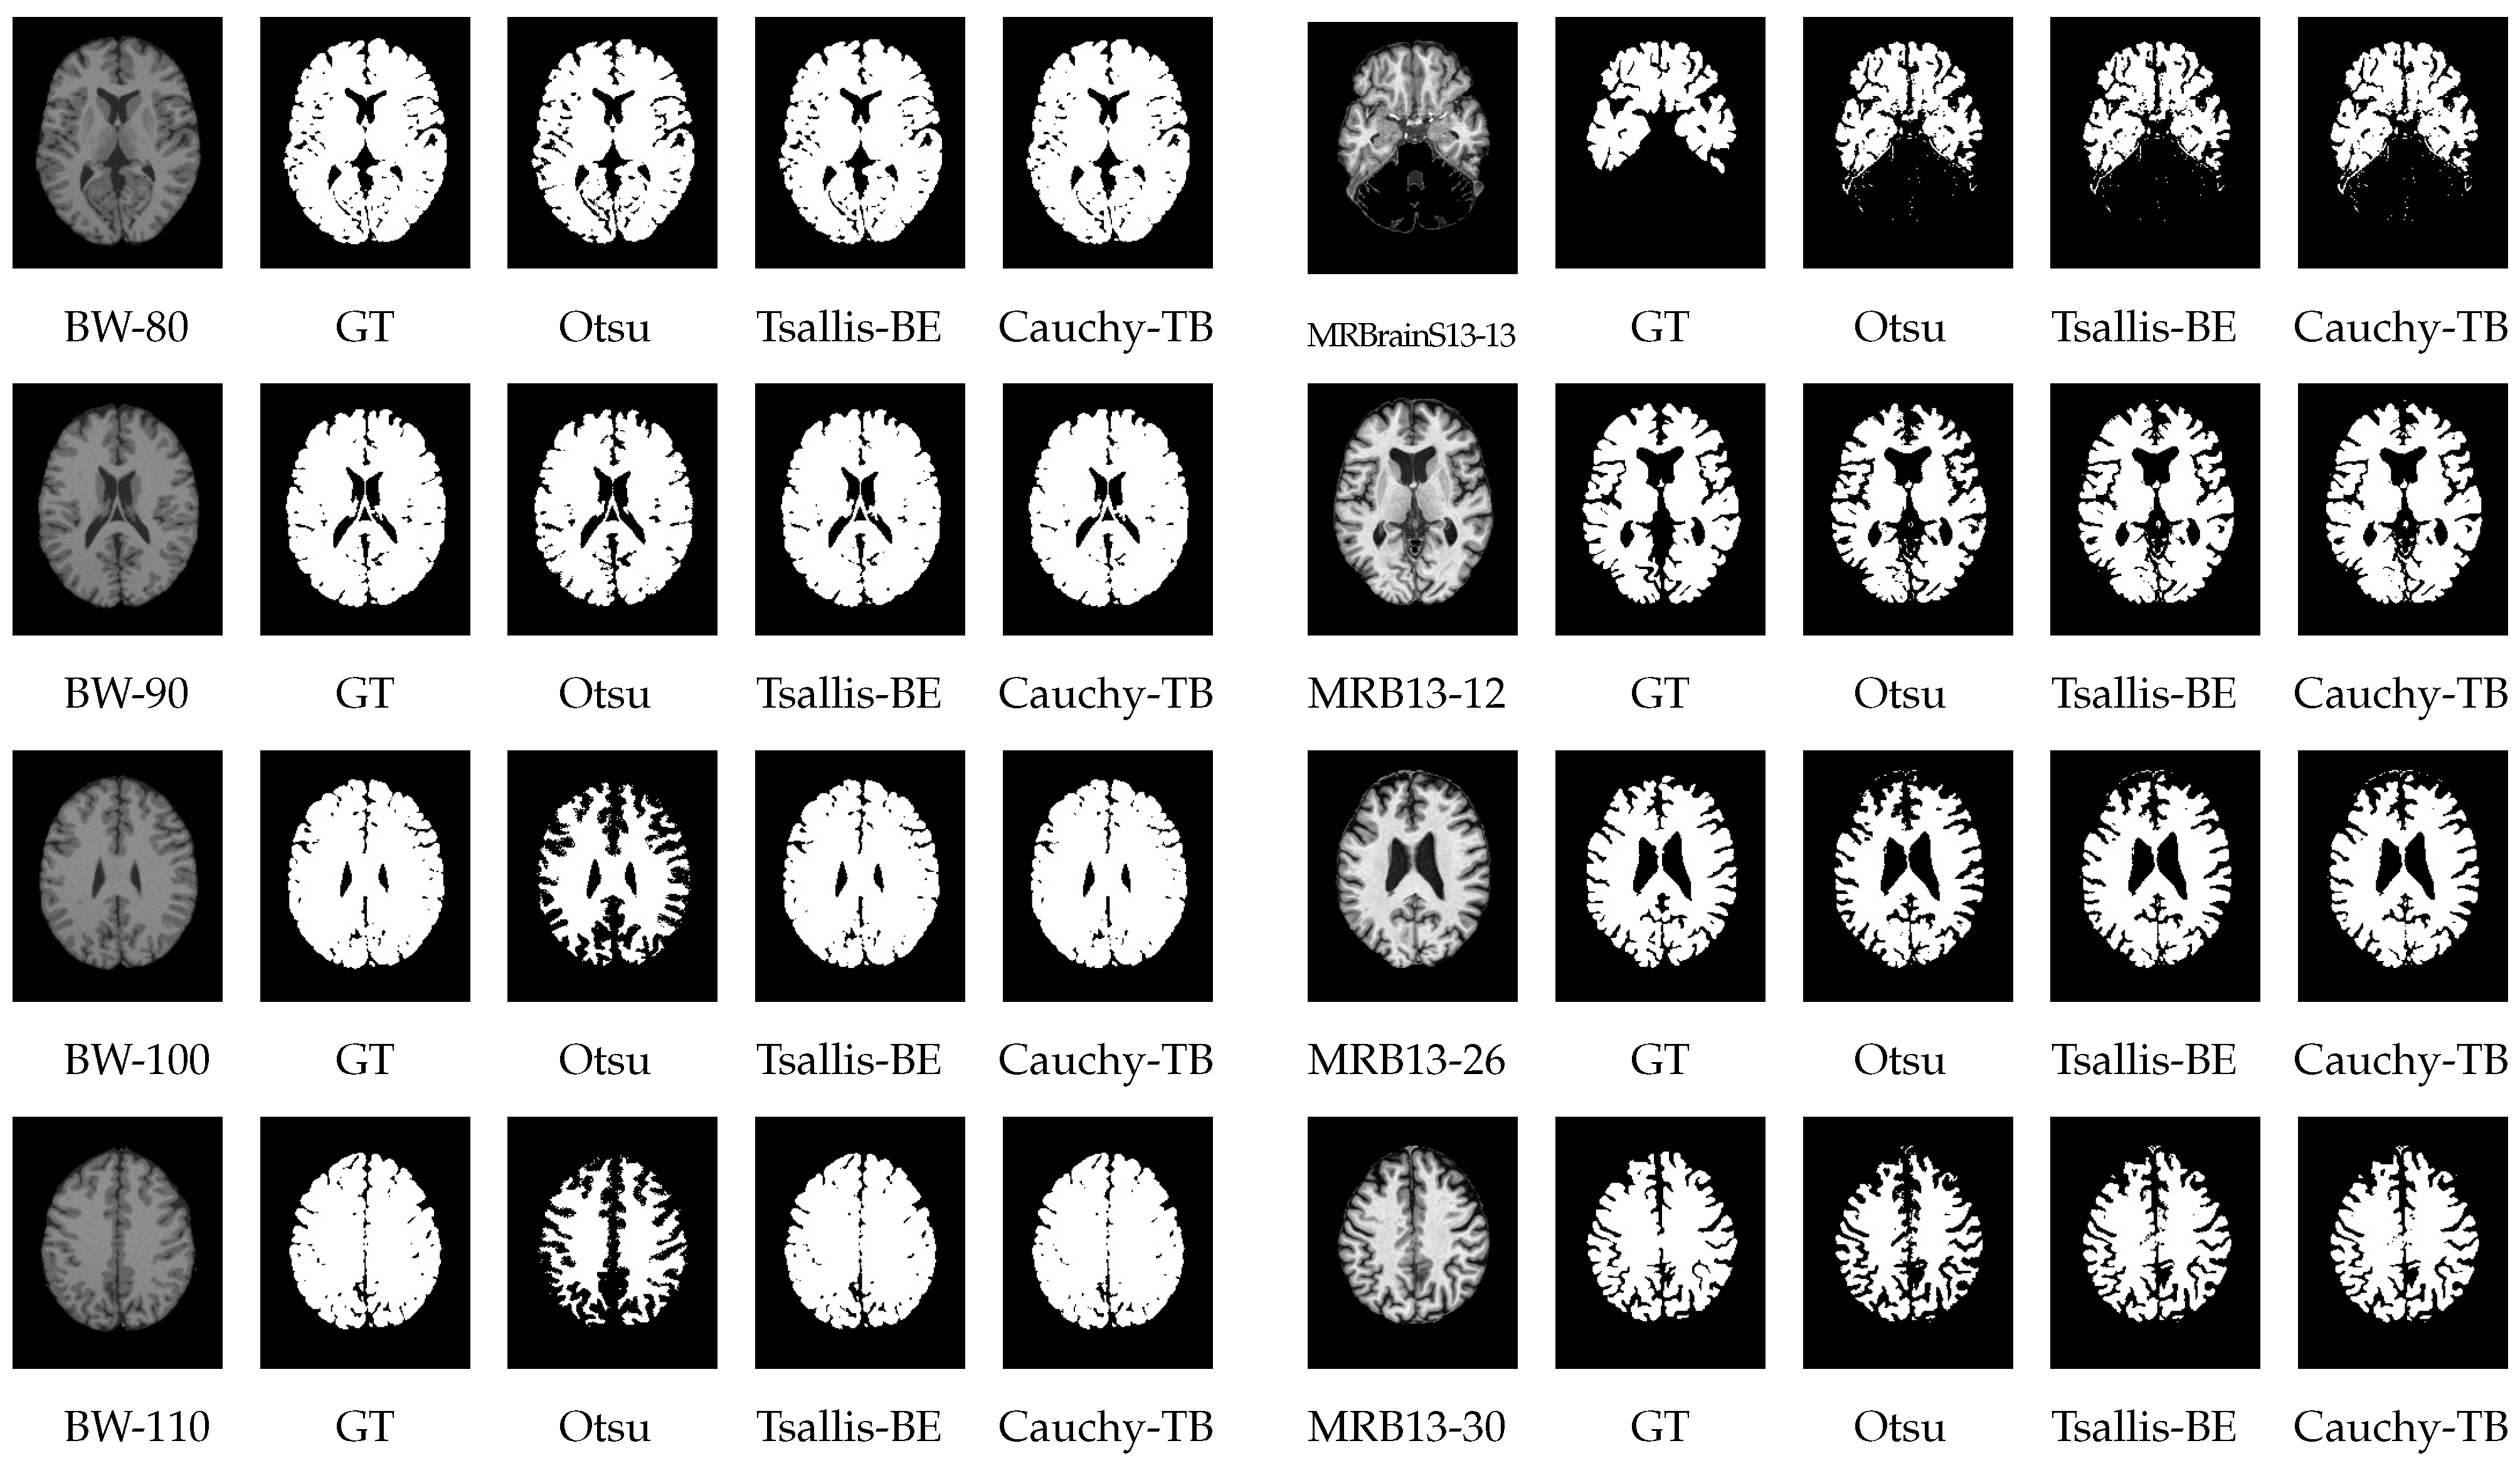

Figure 10 demonstrates the results of image thresholding on some slices taken from the BrainWeb and MRBrainS13 datasets. A comparison revealed that the segmentation achieved by the Otsu method was the worst, showing poor stability in the results. Cauchy-TB and Tsallis-BE were more similar to the ground truth, with the Tsallis-BE method performing well but being slightly inferior to ours in some perceptible details.

Figure 10.

The results of image thresholding by the Cauchy-TB, Otsu, and Tsallis-BE methods. For both the left (BrainWeb) and right (MRBrainS13) groups, the columns from left to right represent the original slice; the ground truth (GT); and the results of Otsu, Cauchy-TB and Tsallis-BE, respectively.